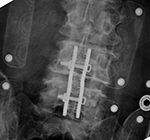

| 85 year-old woman. These images show respectively an AP radiograph of an ILIF at L4-5, an axial CT image of the ILIF, and two coronal reformatted CT images of the ILIF. There is a donar bone plug held in place by the interspinous fixation plate (clamp). |